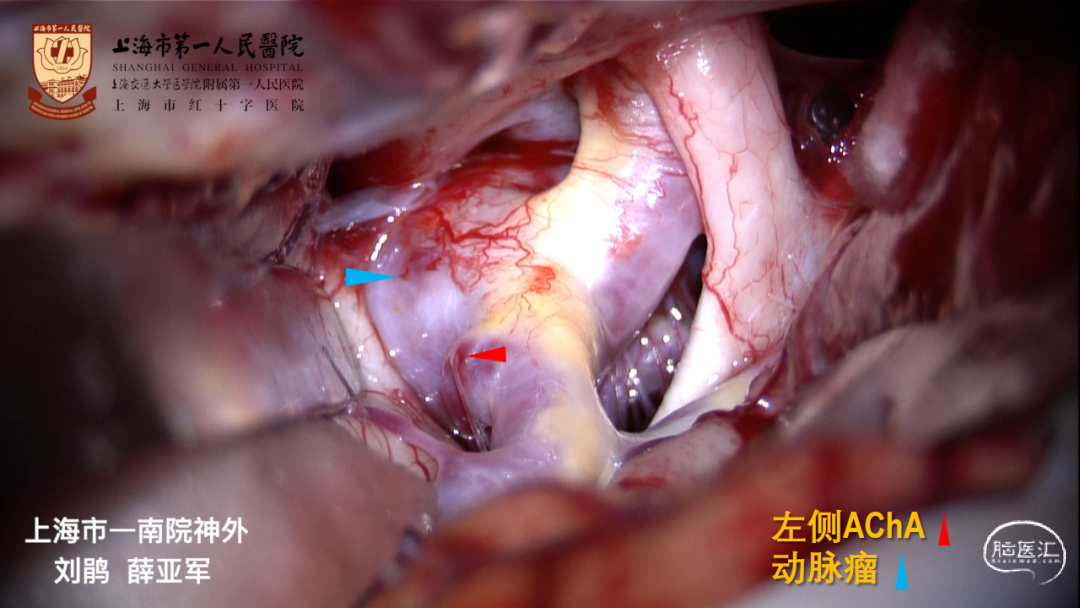

CTA:左侧大型后交通动脉瘤,指向后、外、下

大型动脉瘤,形态复杂:发自ICA后外壁,宽颈、后交通动脉自瘤颈发出

胚胎型后交通动脉,必须保留

术中早期破裂造成手术困难

动脉瘤形态复杂

窗式夹利弊:

窗式夹可用于后壁宽颈动脉瘤

窗式夹释放较困难,不利于保护ICA后、内侧壁发出的穿支